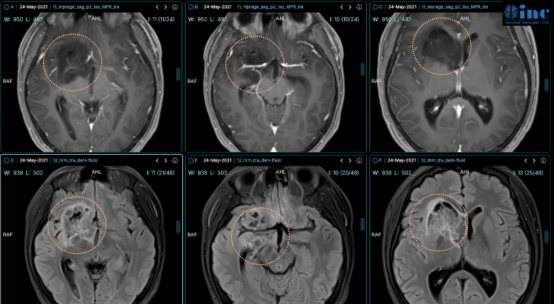

James T. Rutka(鲁特卡)教授,曾任世界神经外科学院院长,现任世界神经外科权威期刊《Journal of Neurosurgery》主编,曾发表题为《Fluid-attenuated Inversion Recovery Ring Sign as a Marker of Dysembryoplastic Neuroepithelial Tumors》(FLAIR高信号环征作为胚胎发育不良性神经上皮肿瘤的标志)的研究论文。该研究详细阐述了DNET患儿在磁共振成像(MRI)上的一个额外特征——即FLAIR序列上的高信号环征。此征象表现出较高的敏感性与特异性,能够辅助术前诊断,并对术后肿瘤残留或复发的评估具有提示作用。

在磁共振成像(MRI)上,DNET在T1加权像(T1WI)上通常表现为均匀或不均匀的低信号;在T2加权像(T2WI)上则表现为均匀或不均匀的高信号。由于其常具有多囊性结构,在T2WI上常呈现典型的“泡泡状”外观。在FLAIR序列上,其信号表现多样,可为高信号或混杂信号,其中高信号“环征”为其典型征象。根据MRI表现,DNET可分为单囊型、多囊型及弥漫型,其中以多囊型最为常见。“泡泡状”外观与高信号“环征”是DNET极具特征性的影像学表现,对临床诊断具有重要的提示价值。

分析结果显示,在9例患者(占82%,敏感性为82%)的FLAIR图像中,可见边界清晰的肿瘤周围高信号环(可为完整环或不完整环)。在作为对照的21例患者中,仅有2例出现了高信号环征(特异性为90%)。病理学分析提示,该高信号环可能与肿瘤周边区域松散的神经胶质细胞成分相关。术后影像学复查中,有3例患者出现了部分残留的环征,而这3例患者均仍存在癫痫发作。另有1例患者在后续接受的第二次手术中被证实存在DNET复发。

该研究结果证实,FLAIR序列上的高信号环征是DNET在MRI上的一个额外特征性表现。此征象具有较高的敏感性(82%)与特异性(90%),可作为术前辅助诊断DNET的一项有用指标。同时,术后影像中若出现该环征,可能提示存在肿瘤残留或复发。